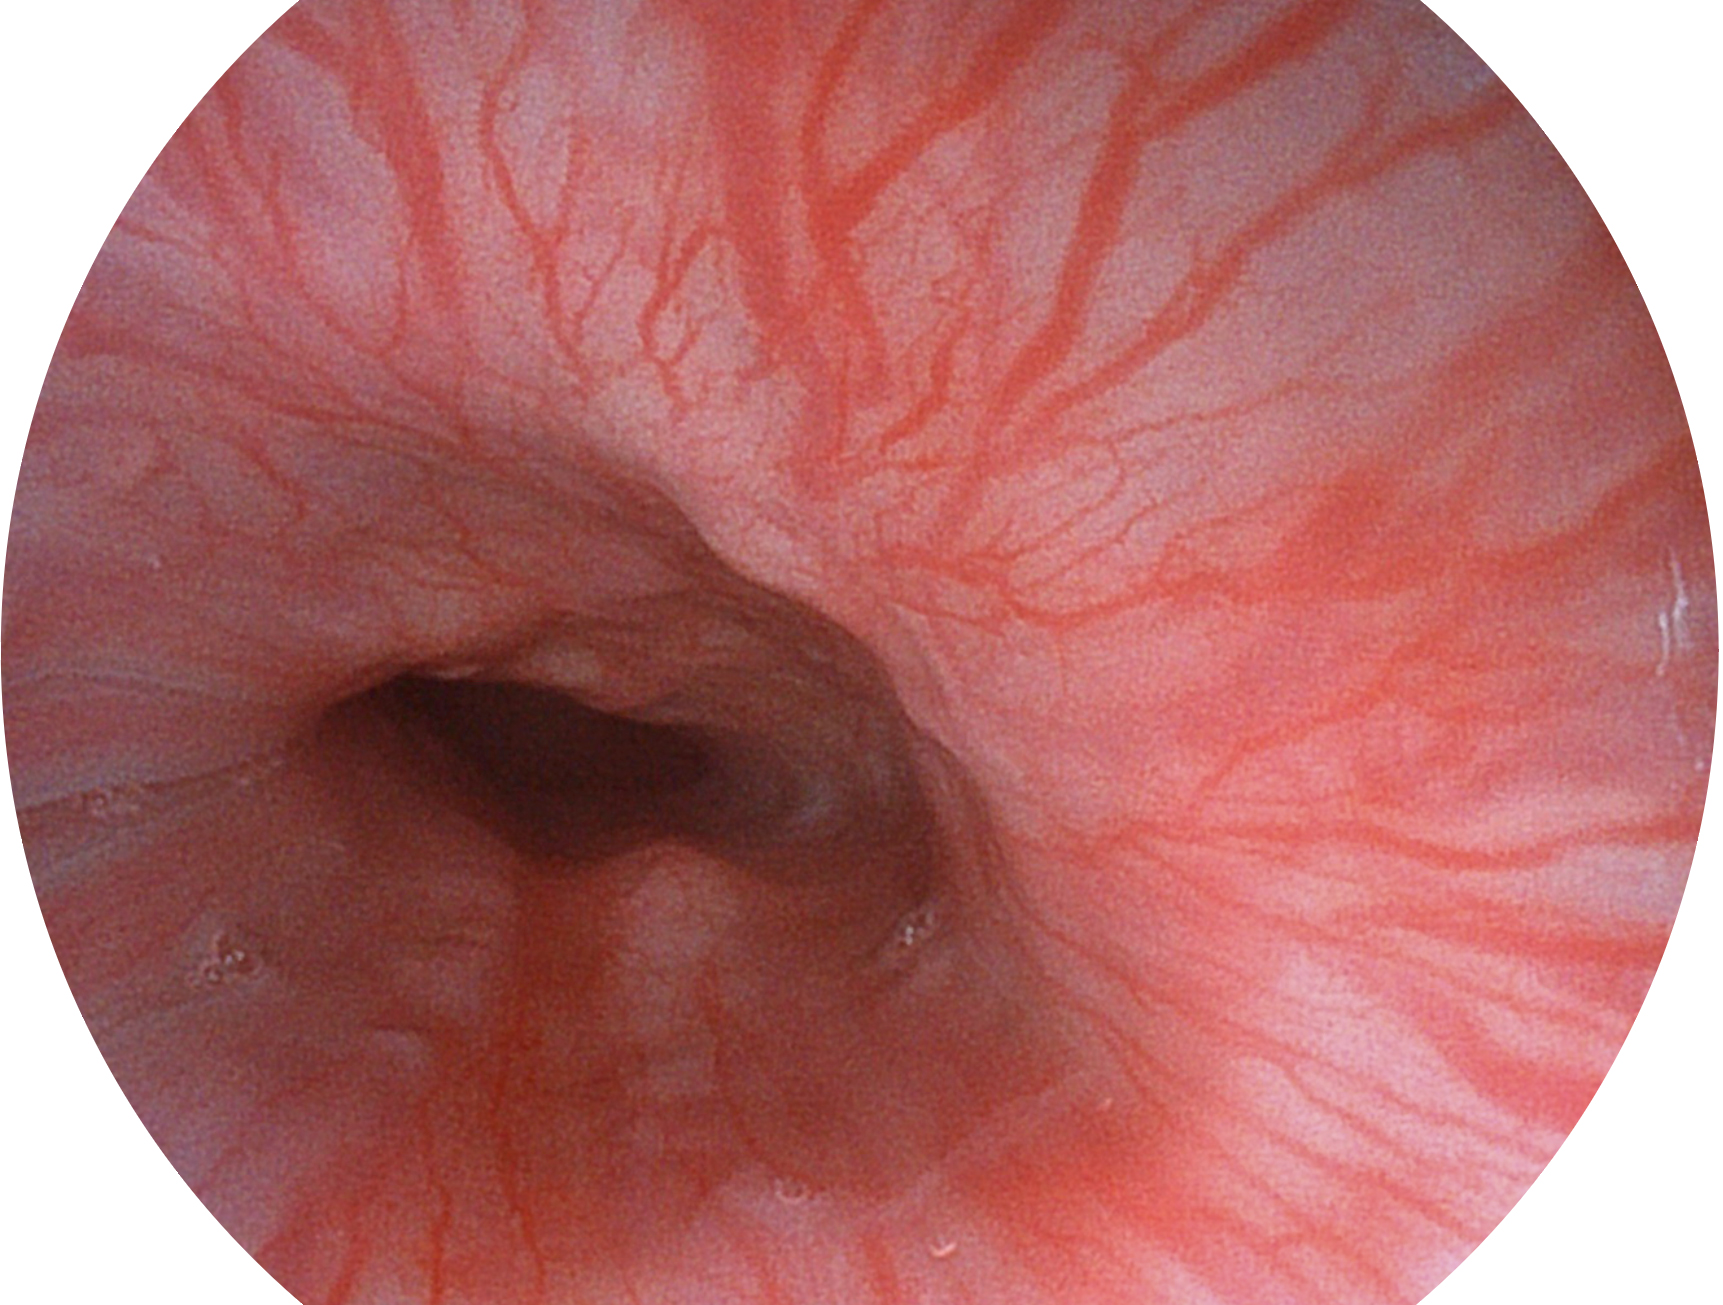

• 白光图像 VIST图像

与上一代VIST相比,摒弃了滤光转轮而直接采用光谱组合的方案,加入了血红蛋白吸收高峰与次高峰的蓝紫光和绿光光谱,更有利于黏膜血管吸收,突显浅表层血管和中层血管的对比度,因而具备更高的图像对比度,近景观察时,有助于微细结构变化及病灶边界的观察。